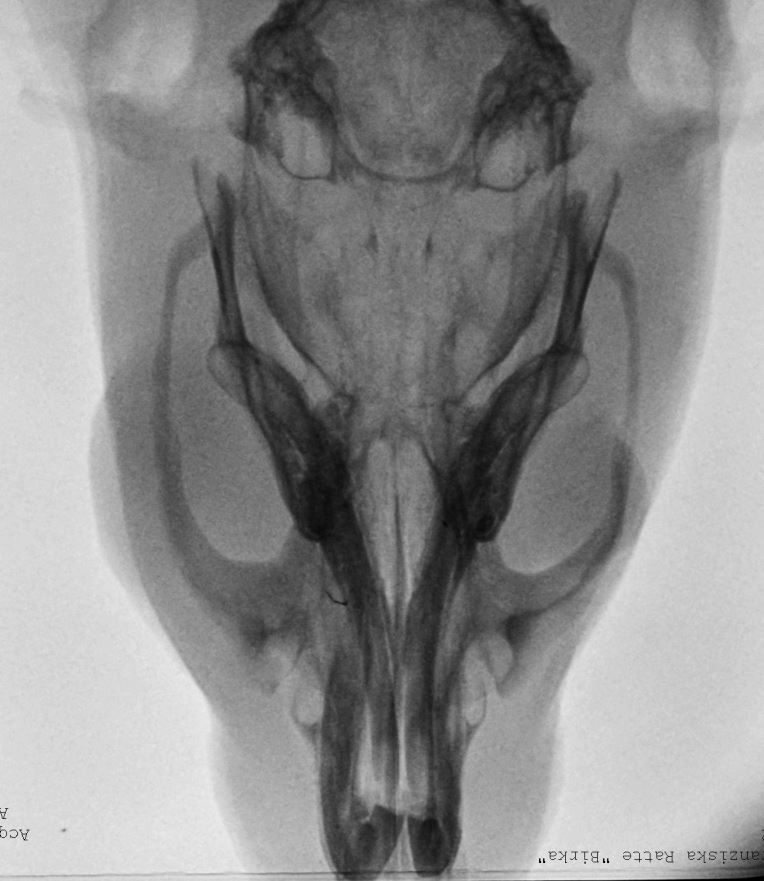

Röntgenbilder: links 14.1. und rechts am Tag der Einschläferung 12.2.

Die Erkrankungsursache der

untersuchten euthanasierten Ratte bestand in einem periorbital

lokalisiertem infiltrativ wachsenden Plattenepithelkarzinom,

einer fibrinös-eitrigen anterioren Uveitis mit assoziierter

erosiv-eitriger Keratitis und einer eitrig-nekrotisierenden

Lymphadentitis.